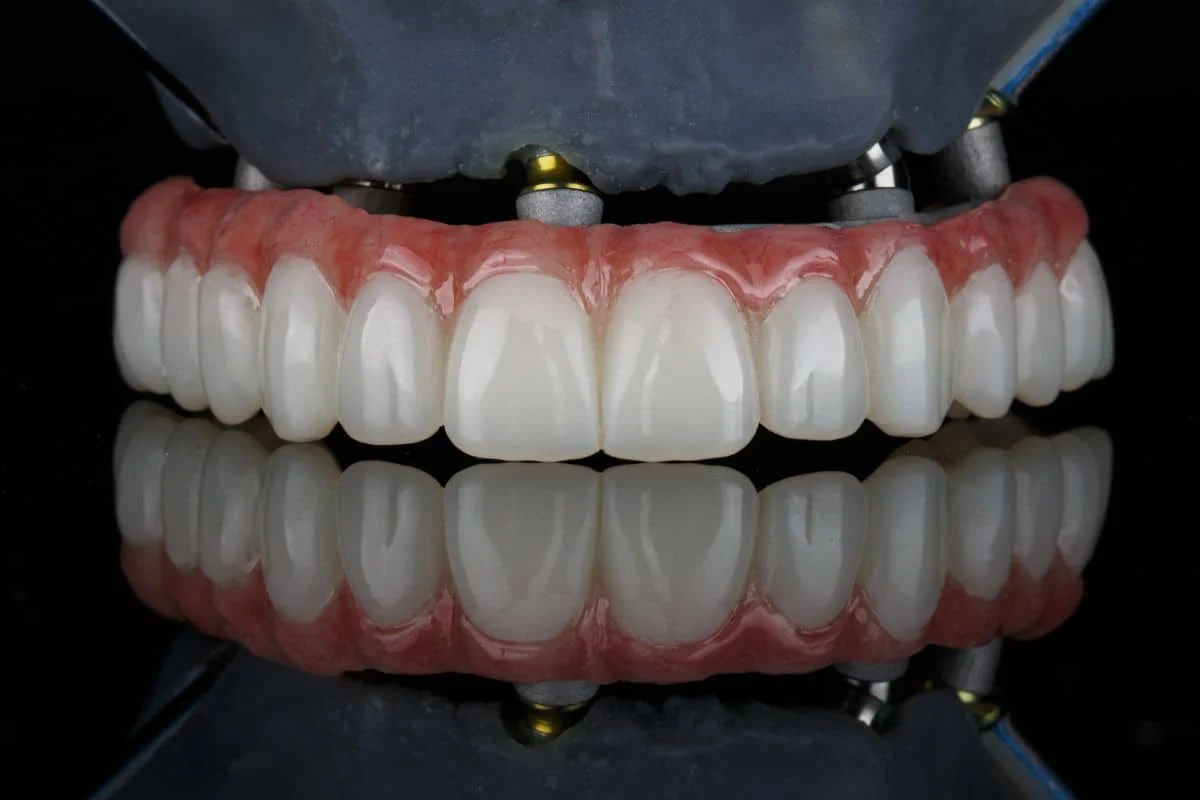

La riabilitazione protesica ha l’obiettivo di sostituire i denti mancanti o gravemente compromessi, restituendo al paziente la piena funzione masticatoria e migliorando l’estetica del sorriso. I principali tipi di protesi coinvolte sono:

- Protesi Fissa: corone, ponti o faccette incollate stabilmente ai denti naturali o a impianti.

La riabilitazione implantare è uno dei pilastri fondamentali della riabilitazione orale moderna. Si tratta di una soluzione innovativa che consente di ripristinare la funzionalità e l’estetica della bocca tramite l’inserimento di impianti dentali, ovvero radici artificiali in titanio, posizionate chirurgicamente nell’osso mascellare o mandibolare.

L’obiettivo della riabilitazione implantare è quello di sostituire i denti naturali in modo stabile e duraturo. Gli impianti fungono da ancoraggio per corone singole, ponti o protesi complete, restituendo al paziente una capacità masticatoria ottimale e un’estetica naturale. - Quando e perché si opta per gli impianti dentali

- Estetica superiore: Le corone su impianto vengono realizzate in materiali altamente estetici, come la ceramica integrale.